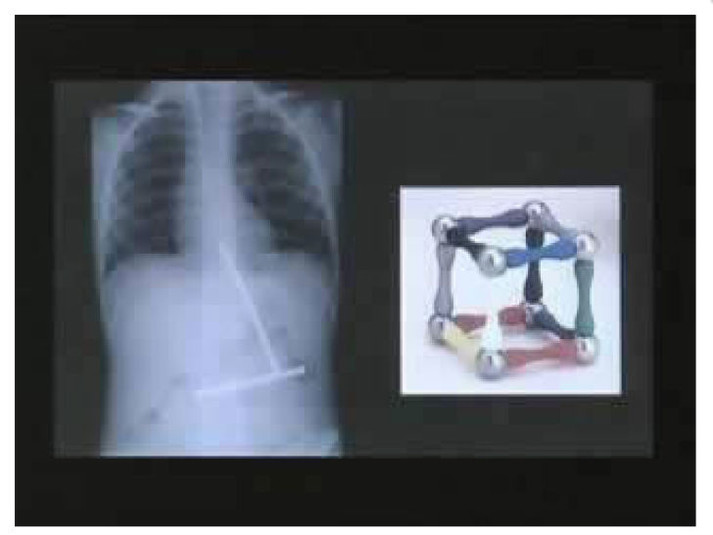

Вот буквально несколько примеров тех вещей, которые были обнаружены в человеческом желудке.